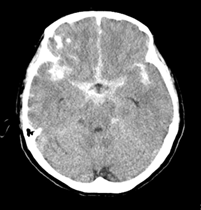

新型コロナワクチンの副反応疑い報告で、現時点で接種との因果関係は評価できていませんが、くも膜下出血と推定される死亡事例(60代女性)が報告されました。くも膜下出血は、40~60歳台に起こりやすく、海外での治験や接種事例でも、新型コロナワクチンとの関連は認められていないとのことです。